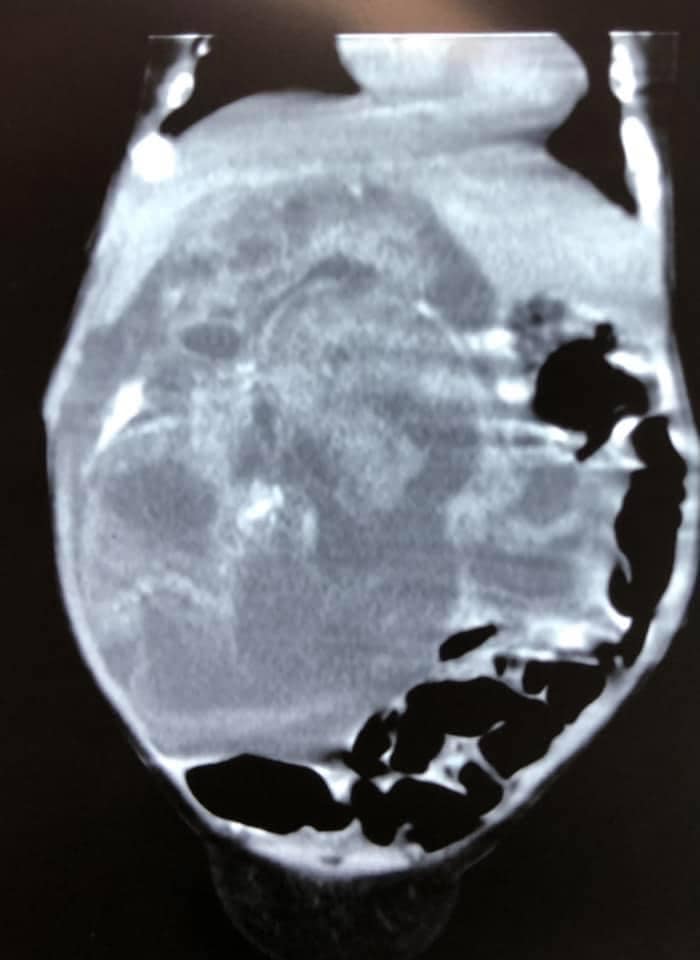

| Хоёр сартай нярайд хагалгаа хийж, нэг кг хавдар авчээ |